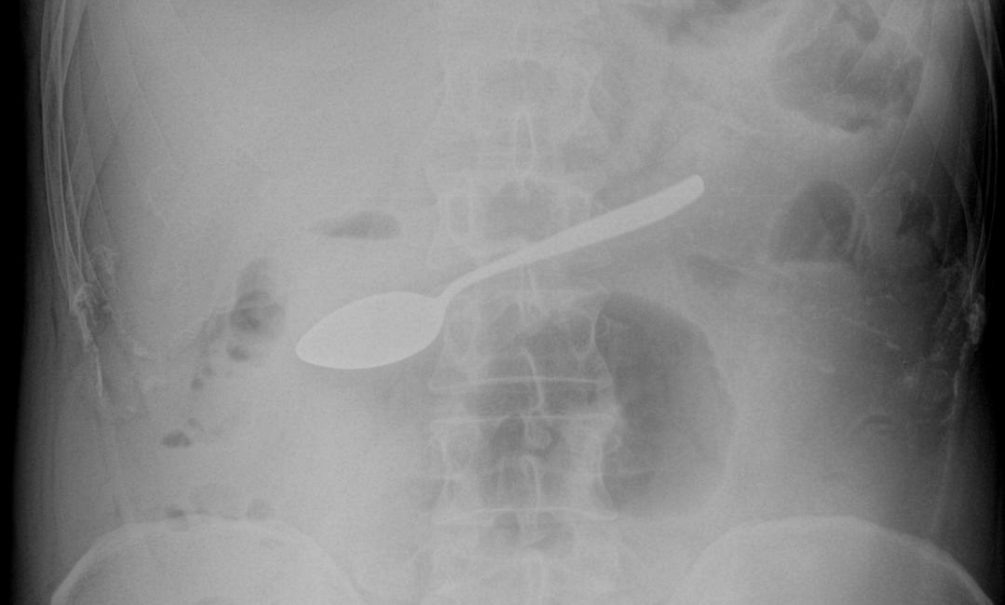

«Проглотил ложку вместо обеда»: в Мытищах врачи вытащили из желудка россиянина десертную ложку

В Мытищинскую больницу Московской области поступил 42-летний мужчина, который жаловался на тошноту, рвоту и повышенное слюноотделение. Медики провели диагностику и нашли в его желудке десертную ложку. Об этом рассказали в пресс-службе министерства здравоохранения Подмосковья. Врач-эндоскопист Максим Щипачев поделился, что прибор пришлось вытаскивать через пищевод с помощью эндоскопического оборудования, чтобы избежать открытой операции. По словам медика, процедура была непростой, потому что на пути к освобождению ложки было несколько сужений, в том числе переход из пищевода в ротоглотку. Однако всё прошло успешно. «Если вовремя не извлечь из пищеварительного тракта крупный металлический предмет, то может начаться угрожающее жизни внутреннее кровотечение. Вероятность того, что предмет беспрепятственно выйдет из организма естественным путём, ничтожна», — поделился Щипачев. На текущий момент мужчина чувствует себя хорошо, его уже выписали и отправили домой лечиться. Он не стал раскрывать

Врач-эндоскопист Максим Щипачев поделился, что прибор пришлось вытаскивать через пищевод с помощью эндоскопического оборудования, чтобы избежать открытой операции. По словам медика, процедура была непростой, потому что на пути к освобождению ложки было несколько сужений, в том числе переход из пищевода в ротоглотку. Однако всё прошло успешно.

«Если вовремя не извлечь из пищеварительного тракта крупный металлический предмет, то может начаться угрожающее жизни внутреннее кровотечение. Вероятность того, что предмет беспрепятственно выйдет из организма естественным путём, ничтожна», — поделился Щипачев.

На текущий момент мужчина чувствует себя хорошо, его уже выписали и отправили домой лечиться. Он не стал раскрывать истории, как десертная ложка оказалась у него в таком необычном месте.